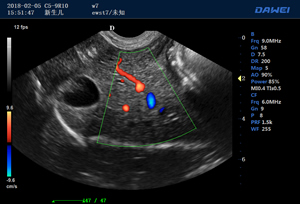

·支持B、C、PW、CW、寬景成像

適用于各種動物的臨床腹部、胸腔,心臟、肌腱、小器官、眼球、生殖系統等的檢查